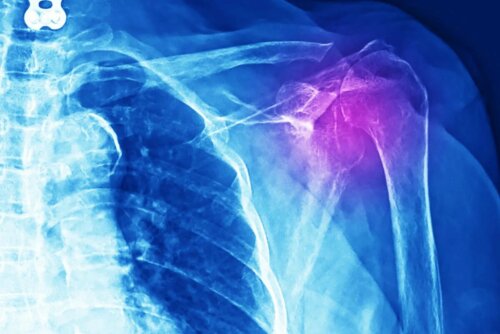

Außerdem führt der Arzt mehrere Untersuchungen durch, um diese Verletzung zu diagnostizieren, darunter Röntgenaufnahmen, Ultraschall, MRT und sogar eine Computertomographie. Ein weiterer Schritt sind eine ärztliche Untersuchung und eine ausführliche Analyse der Krankengeschichte des Patienten.